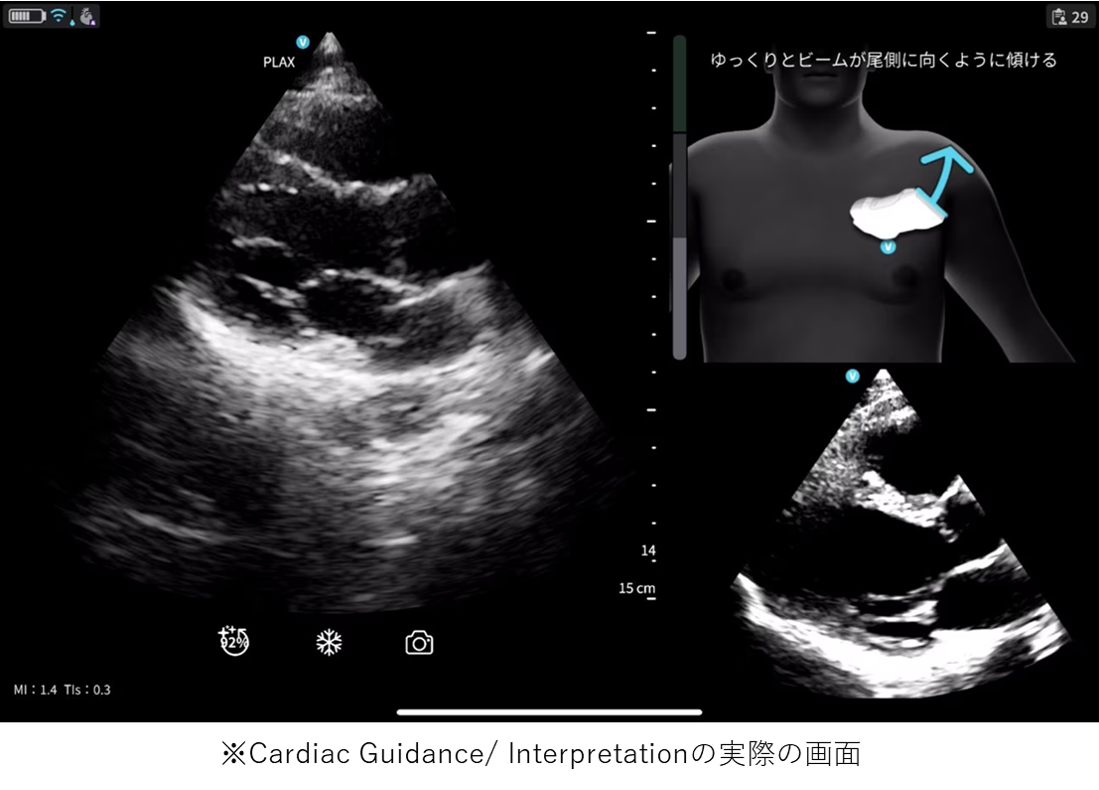

「Vscan Air SL Ally」には、心エコー検査をサポートするCardiac Guidance機能とCardiac Interpretation機能が備わっています。Cardiac Guidanceは、検査手技をAIがリアルタイムでガイドしながら、画像の品質を担保し、一方のCardiac Interpretationは、取得した画像をAIが解析し、診断精度を引き上げます。

リアルタイムで操作者をサポートするガイド機能で、プローブ(探触子)の位置、角度、肋間操作、深度を画面上で指示し、より正確で高品質な画像取得をサポートします。さらに、画像品質のインジケータ機能を備えており、最適なスキャン画像が得られているか否かを判定します。また、一定レベル以上の品質を認識した際には、プローブを一定時間保持することで自動的に画像を保存します。Cardiac Guidanceの機能により、複雑な心エコー検査を簡便かつ正確に実施することが可能となり、臨床現場だけでなく、大学や基幹病院のトレーニングセンターでの教育利用にも「Vscan Air SL Ally」の導入が期待されます。